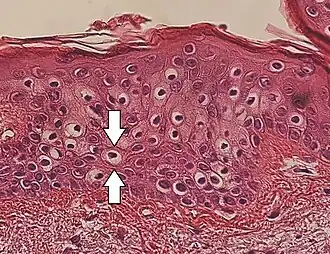

Vacuolization

Vacuolization is the formation of vacuoles or vacuole-like structures, within or adjacent to cells. Perinuclear vacuolization of epidermal keratinocytes is most likely inconsequential when not observed in combination with other pathologic findings. In dermatopathology "vacuolization" often refers specifically to vacuoles in the basal cell-basement membrane zone area, where it is an unspecific sign of disease.[1] It may be a sign of for example vacuolar interface dermatitis, which in turn has many causes.